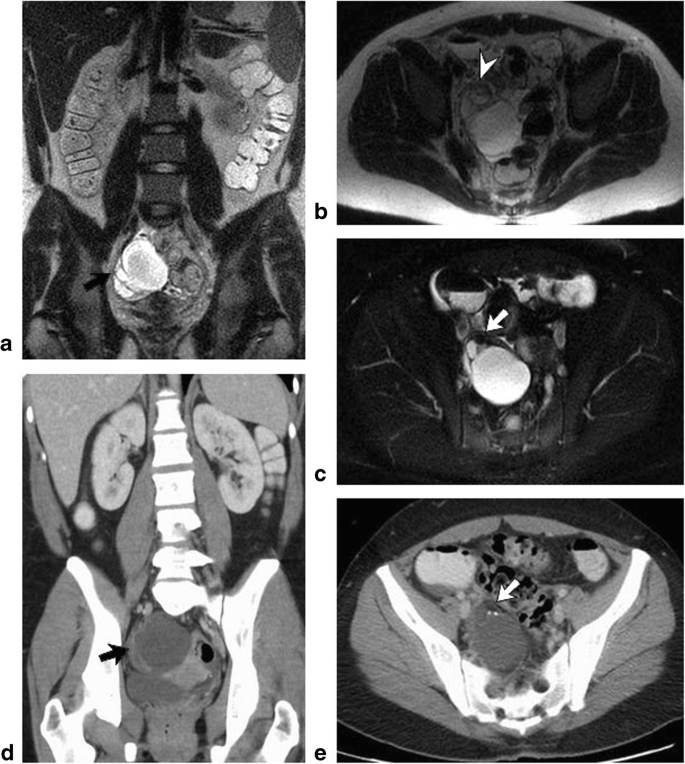

An MRI Pelvis Scan is a non-invasive, radiation-free imaging test used to examine the pelvic organs and soft tissues. It uses powerful magnetic fields and radio waves to produce detailed images of the uterus, ovaries, prostate, bladder, rectum, pelvic bones, muscles, and blood vessels.

Detect uterine fibroids, ovarian cysts, or endometriosis

Identify pelvic tumors or masses